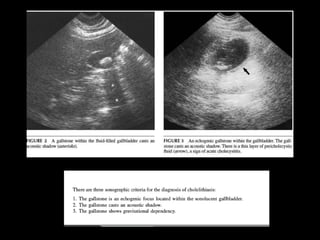

TYPICAL SONOGRAPHIC

APPEARANCE OF

GALLSTONE

UNDER WHAT CIRCUMSTANCES

WOULD THE GALLBLADDER NOT

HAVE ITS TYPICAL APPEARANCE?

• When patient has recently eaten.

• Multiple episodes of cholecystitis (scarred and

shrunken)

• Filled w/stones or contracted around

gallstones

• Air filled gallblader (empysematouse

cholecystitis)

WALL-ECHO-SHADOW (WES) OR DOUBLE ARC

TYPICAL SONOGRAPHIC APPEARANCE OF GALLSTONE

UNDER WHAT CIRCUMSTANCES WOULDTHE GALLBLADDER NOT HAVE ITS TYPICAL APPEARANCE?

• When patienthas recently eaten. • Multiple episodes of cholecystitis (scarred and shrunken) • Filled w/stones or contracted around gallstones • Air filled gallblader (empysematouse cholecystitis)